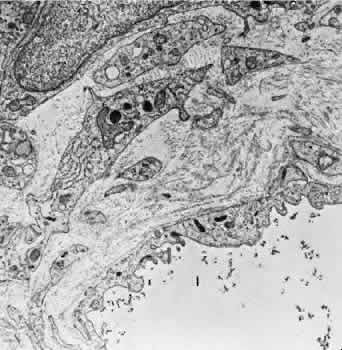

With aging, the connective tissue adjacent toand surrounding the choriocapillaris undergoeschanges, and electron-dense filaments and wide-spacing collagen may be seen. The main nerve supply to the choroid is from the ciliary nerves. A significant proportion of the fibers innervate the blood vessels and belong to the sympathetic nervous system. Delicate plexuses and ganglion cells are found in the surrounding connective tissue, and unmyelinated fibers course toward the vessel wall.62 CILIARY BODY AND IRIS The arterial blood supply to the ciliary body is from the branches of the long PCA, branches of the anterior ciliary arteries, and branches from the major arterial circle. Funk and Rohen,63 using scanning electron microscopy of resin casts of the ciliary body and iris vessels, have contributed significantly to our understanding of the anatomy of these vessels. They found that the perforating branches of the anterior ciliary arteries form an intramuscular circle that supplies the outer and posterior portions of the ciliary muscle, the iris, and the anterior choroid. The major circle of the iris is located more anteriorly and is supplied by the long PCAs and branches from the anterior ciliary arteries. The iridic major circle contributes to the anterior supply of the ciliary body as well as to the iris and ciliary processes. The ciliary processes themselves have three distinct vascular territories, each with its own system of arterioles and venules.63 The small arteries of the stroma of the ciliary body contain an endothelium and basement membrane, a poorly developed elastic lamina, a media containing two or three layers of smooth muscle, and a loose collagenous adventitia. Most ciliary vessels drain posteriorly into the choroidal and vortex systems. The remaining drainage is into the intrascleral venous plexus and the episcleral veins of the limbal region. Small veins and venules are found in the ciliary processes along with the capillaries. These vessels are often closely apposed to the pigmented layer of the epithelium surrounding the ciliary processes. The capillaries and venules of the ciliary body are 15 to 30 μm in diameter and are fenestrated in both the pars plicata and pars plana. They closely resemble the capillaries of the choriocapillaris except that they are smaller. The fenestrae of these vessels range in size from 300 to 1,000 nm in diameter.64 The major difference between the capillaries in different areas of the ciliary body is that only those of the pars plana are in contact with the elastica of Bruch's membrane on the surface facing the pigmented epithelium. The capillaries present in the ciliary muscle are nonfenestrated (Figs. 16 and 17). The blood vessels are innervated by small branches of sympathetic fibers. The iris blood vessels derive from the major iridic arterial circle and drain into the vortex system. The blood vessels of the iris are believed to have a slight corkscrew shape so they can accommodate to the changes in the length of the iris during dilation and contraction. A striking finding in all the iris vessels is the presence of thick collagenous adventitia that is several microns thick. There are approximately 200 radial vessels in the iris. The density of these vessels is greater than expected for the nutrition of the iris, and they probably account for anterior-segment thermal homeostasis and provide a high oxygen content for the corneal endothelium. Most of the vessels in the iris stoma are arterioles (Figs. 18, 19, and 20), venules, and capillaries (Fig. 21). The capillaries have unfenestrated endothelium with tight junctions. The main branches of these radial vessels form an incomplete circular arterial ring at the collarette (minor iris circle). Branches from the minor circle extend into the pupillary region to form capillary arcades. The venous drainage system parallels the arterial inflow pattern. The radial arteries of the iris are truly arterioles, with an overall diameter of 15 to 50 μm. The radial iridial veins are technically pericytic venules. They are approximately 30 to 90 μm in diameter. The media consists of one or two layers of pericytes. These cells make frequent contact with the endothelial cells but not with each other.